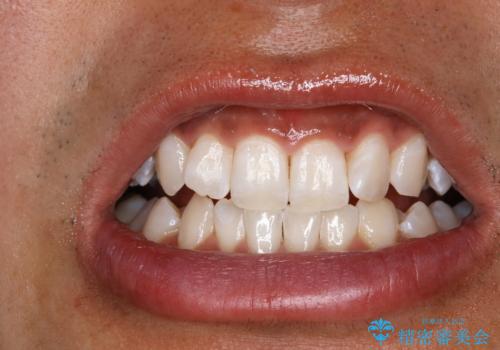

処置後は艶のある綺麗な白さになりました。

ご希望の自然な白さに、トーンアップしたとのことで満足していただけました。